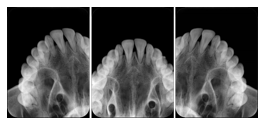

2 Occlusal Vertical Maxilla A Dental Image Layout

DL-C001A

Reference: DL-C001-U1L0

Reference: DL-C001-U2L0

00

Occlusal

18, 17, 16, 15, 14, 13, 12, 11, 13, 12, 11

01

21, 22, 23, 24, 25, 26,27, 28

2 Occlusal Vertical Mandible A Dental Image Layout

DL-C002A

Reference: DL-C002-U0L1

Reference: DL-C002A-U0L2

10

48, 48, 47, 46, 45, 44, 43, 42, 41

11

31, 32, 33, 34, 35, 36, 37, 38

2 Occlusal Horizontal Maxilla A Dental Image Layout

DL-C003A

Reference: DL-C003-U1L0

Reference: DL-C003-U2L0

18, 17, 16, 15, 14, 13, 12, 11, 13, 12, 11, 21, 22, 23, 24, 25, 26,27, 28

2 Occlusal Horizontal Mandible A Dental Image Layout

DL-C004A

Reference: DL-C004-U0L1

Reference: DL-C004-U0L2

48, 48, 47, 46, 45, 44, 43, 42, 41, 31, 32, 33, 34, 35, 36, 37, 38